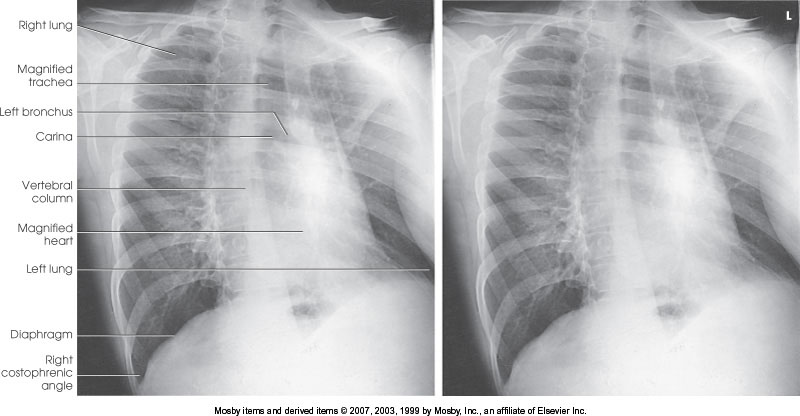

What position is demonstrated?

Lateral Chest